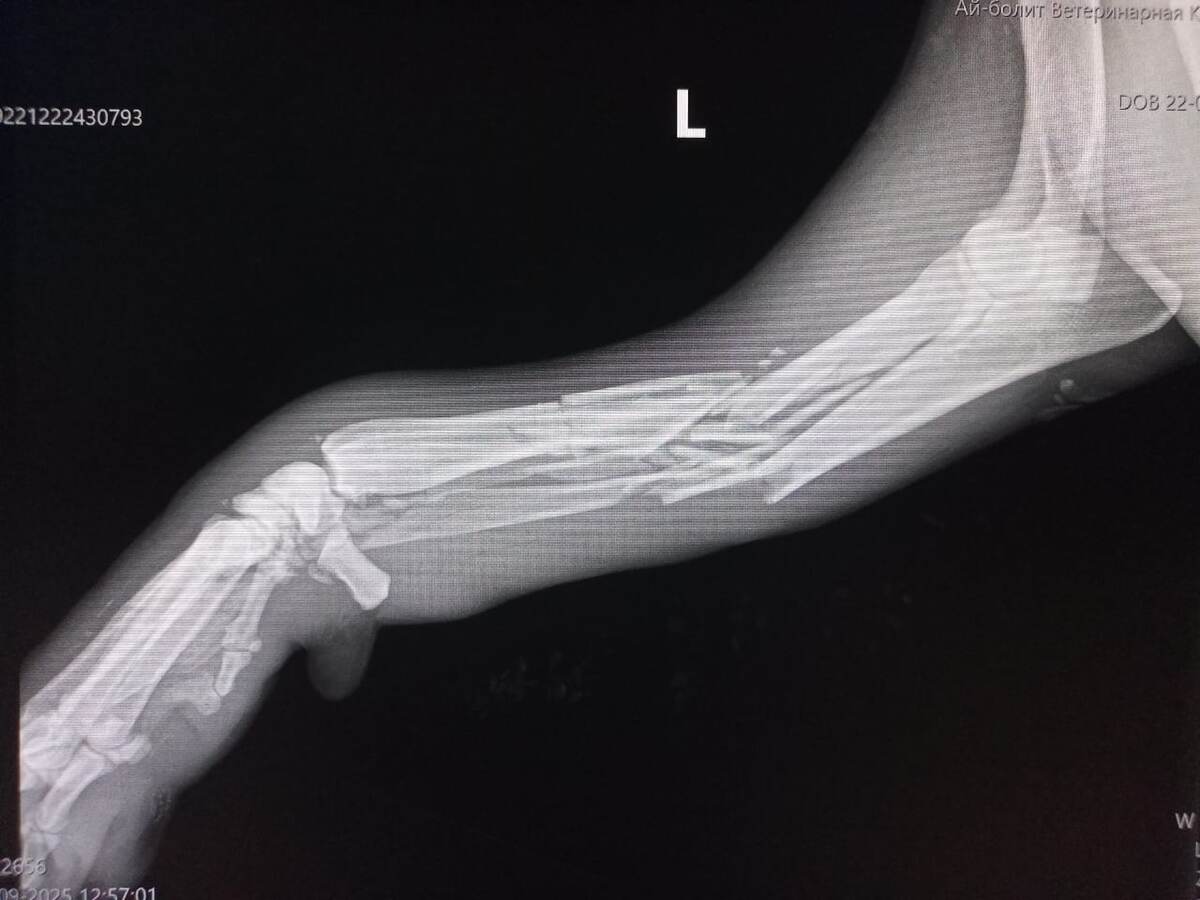

У Тедди переломы обеих передних лап.

Одна лапа - перелом со смещением.

Вторая лапа висит как тряпочка. Кость раздроблена.

Нужно оперировать обе лапы. На раздробленную нужно ставить аппарат Илизарова.

Операция назначена на 26 сентября. Нам необходимо собрать на оплату не менее 30 тысяч рублей. Возможно, что и дороже обойдется.